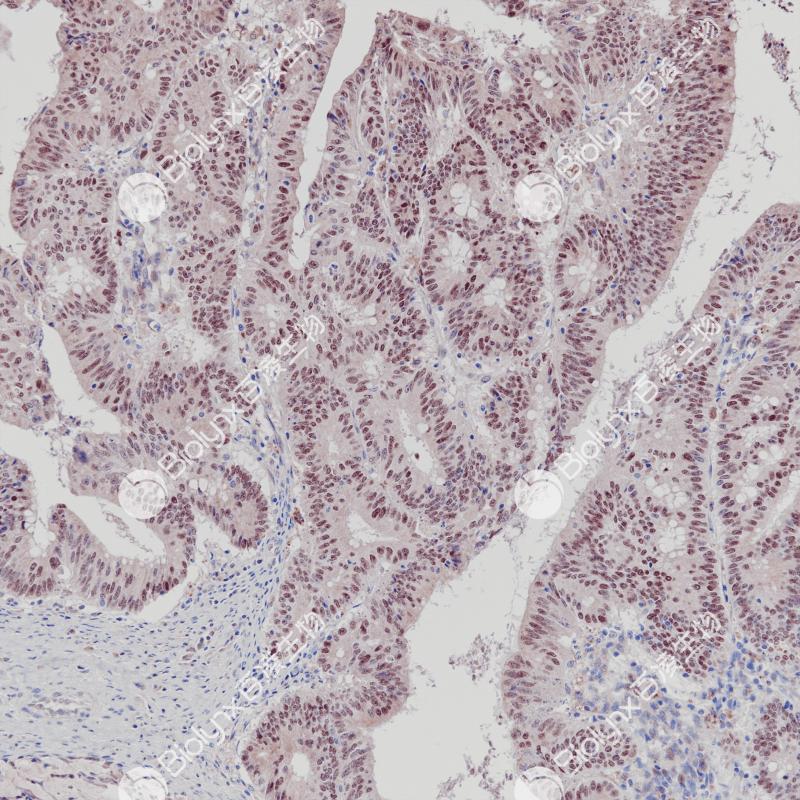

c-Myc 重组兔单克隆抗体

阳性对照

伯基特淋巴瘤

亚细胞定位

细胞核